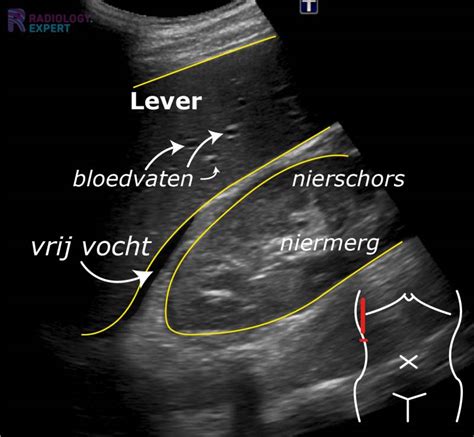

- Echografie: Met een echo kan de zwangerschap vanaf ongeveer dag 21 tot 28 na de ovulatie worden bevestigd. Tussen dag 25 en 30 is dit vaak optimaal. Een echo biedt visuele bevestiging van de foetussen en hun ontwikkeling.